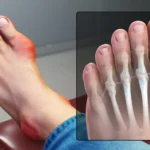

কালো দাগ-

কনুই, পায়ে কালো দাগ। হাজার চেষ্টা করার পরেও এটি দূর করা যায় না। অথবা কিছুক্ষণ চেয়ারে বসে থাকার পরেও পা ফুলে যায়। এটি অবশ্যই রক্তে শর্করার ফলে হয়। তাই যদি আপনি এই লক্ষণগুলি দেখেন, তাহলে সরাসরি ডাক্তারের কাছে যান। আপনার রক্তে শর্করার দিকে নজর রাখুন।